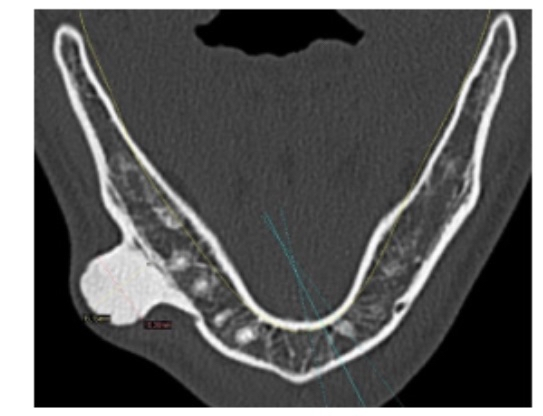

In another individual case, a woman hit her finger on a cabinet, leading to a hematoma, which then ossified into new bone [31]. In another case, a Muay Thai boxer experienced massive bone hypertrophy clearly visible on X-ray, which scientists attributed to repeated microtrauma [32]. In another individual case, a child fell on their pelvis while skiing, and radiographs showed very dense bone hypertrophy at the injury site due to a subperiosteal hematoma (see figure 4 to view the hypertrophy) [33].

(Figure 4, an image showing a dense bony mass resulting from the periosteum being lifted off the bone layer and ossification of the hematoma)